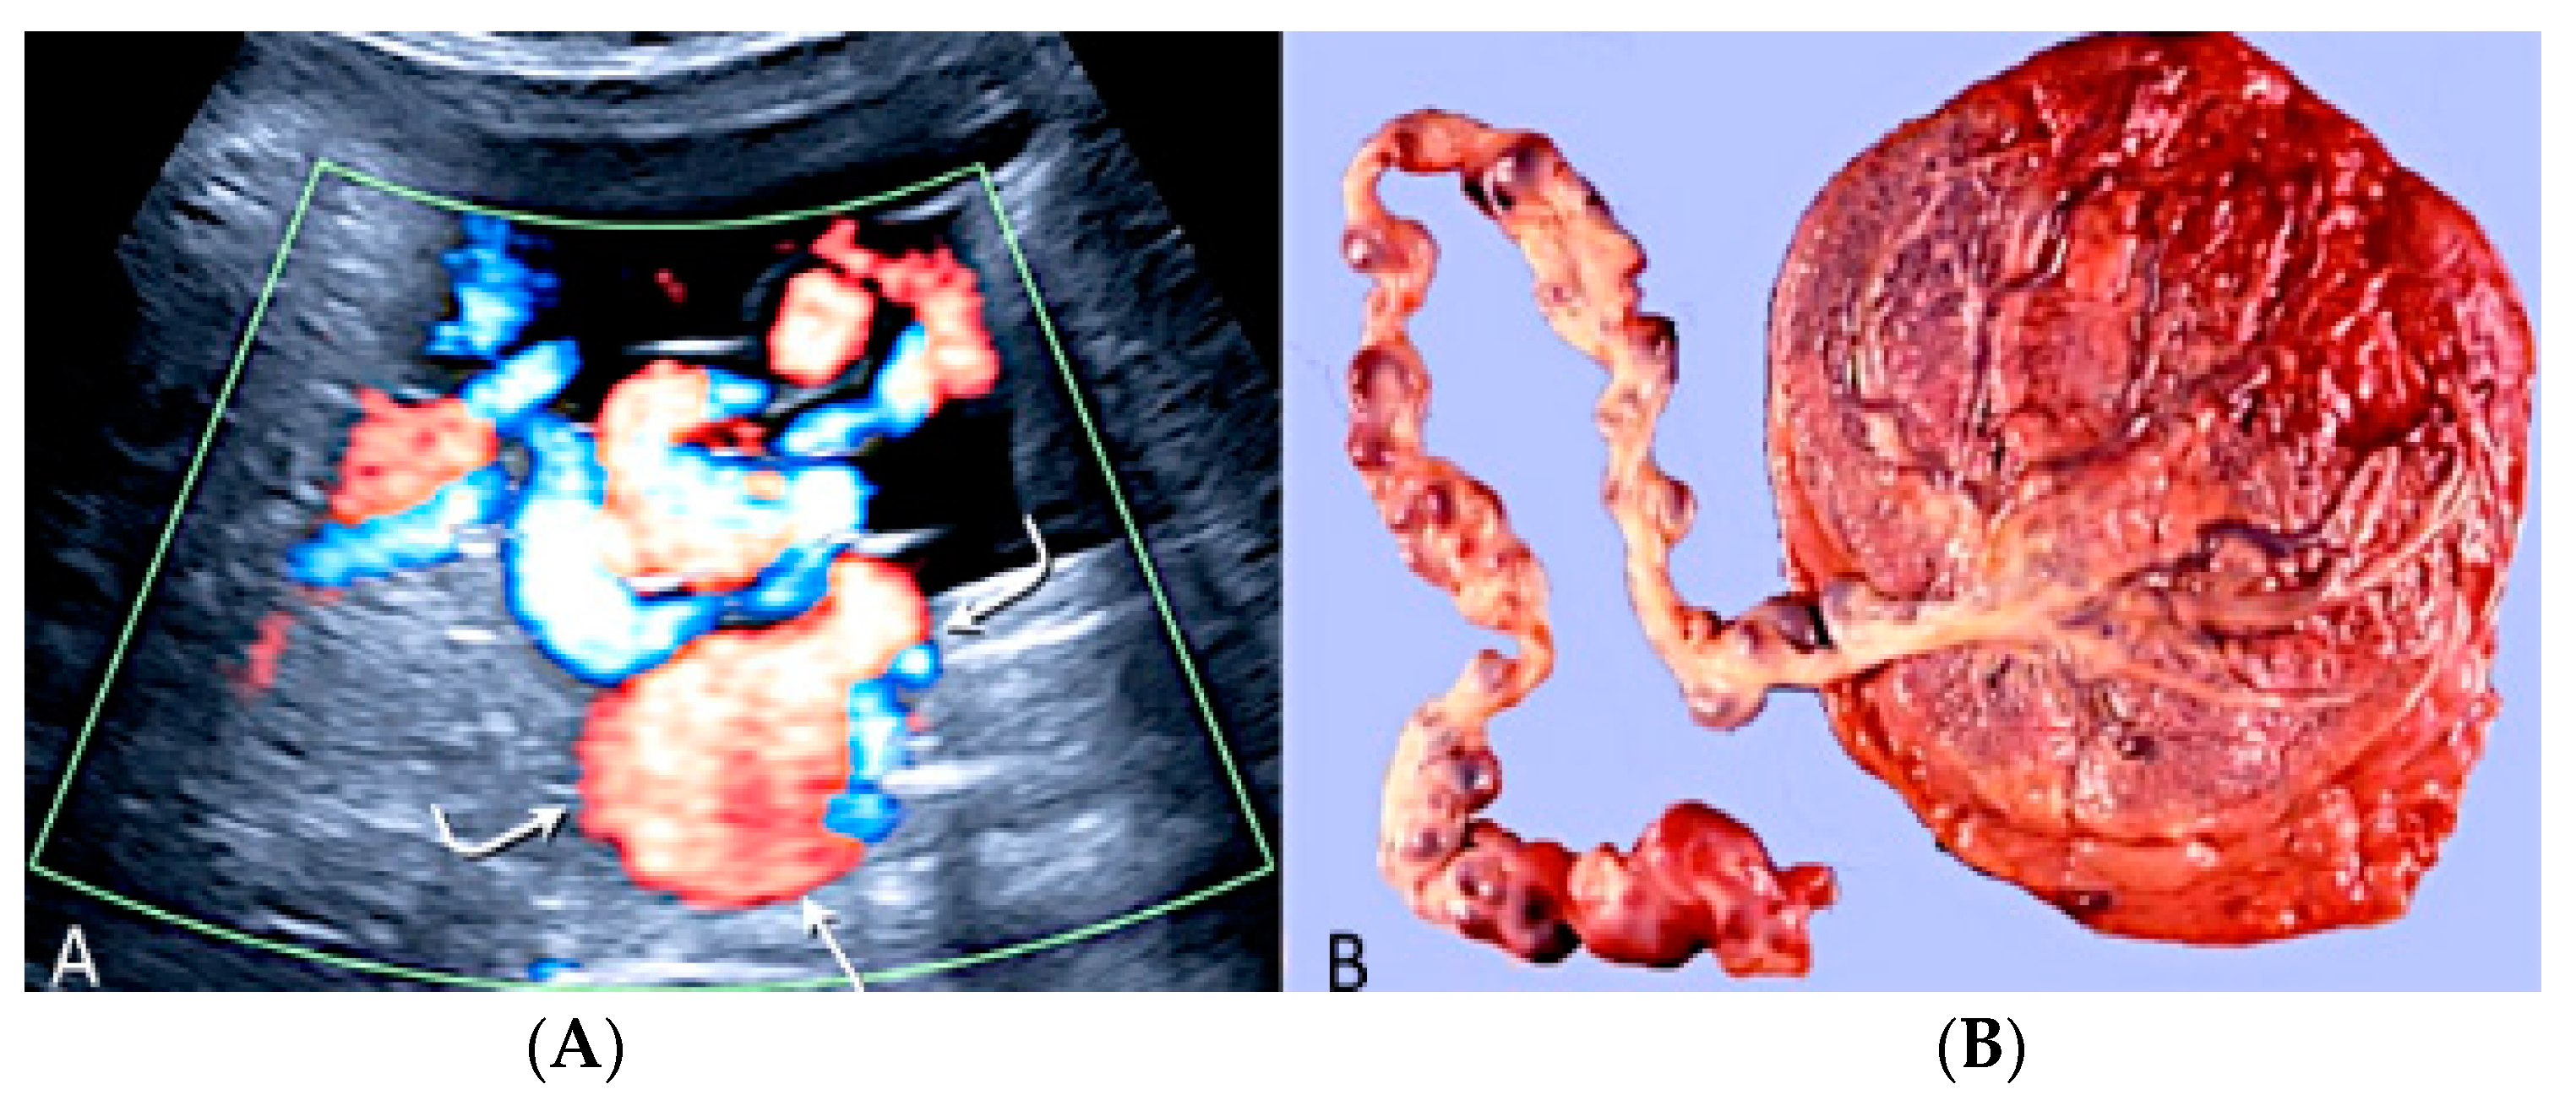

3.1.6. Chorioangioma

3.1.7. Membranous Placental Cysts